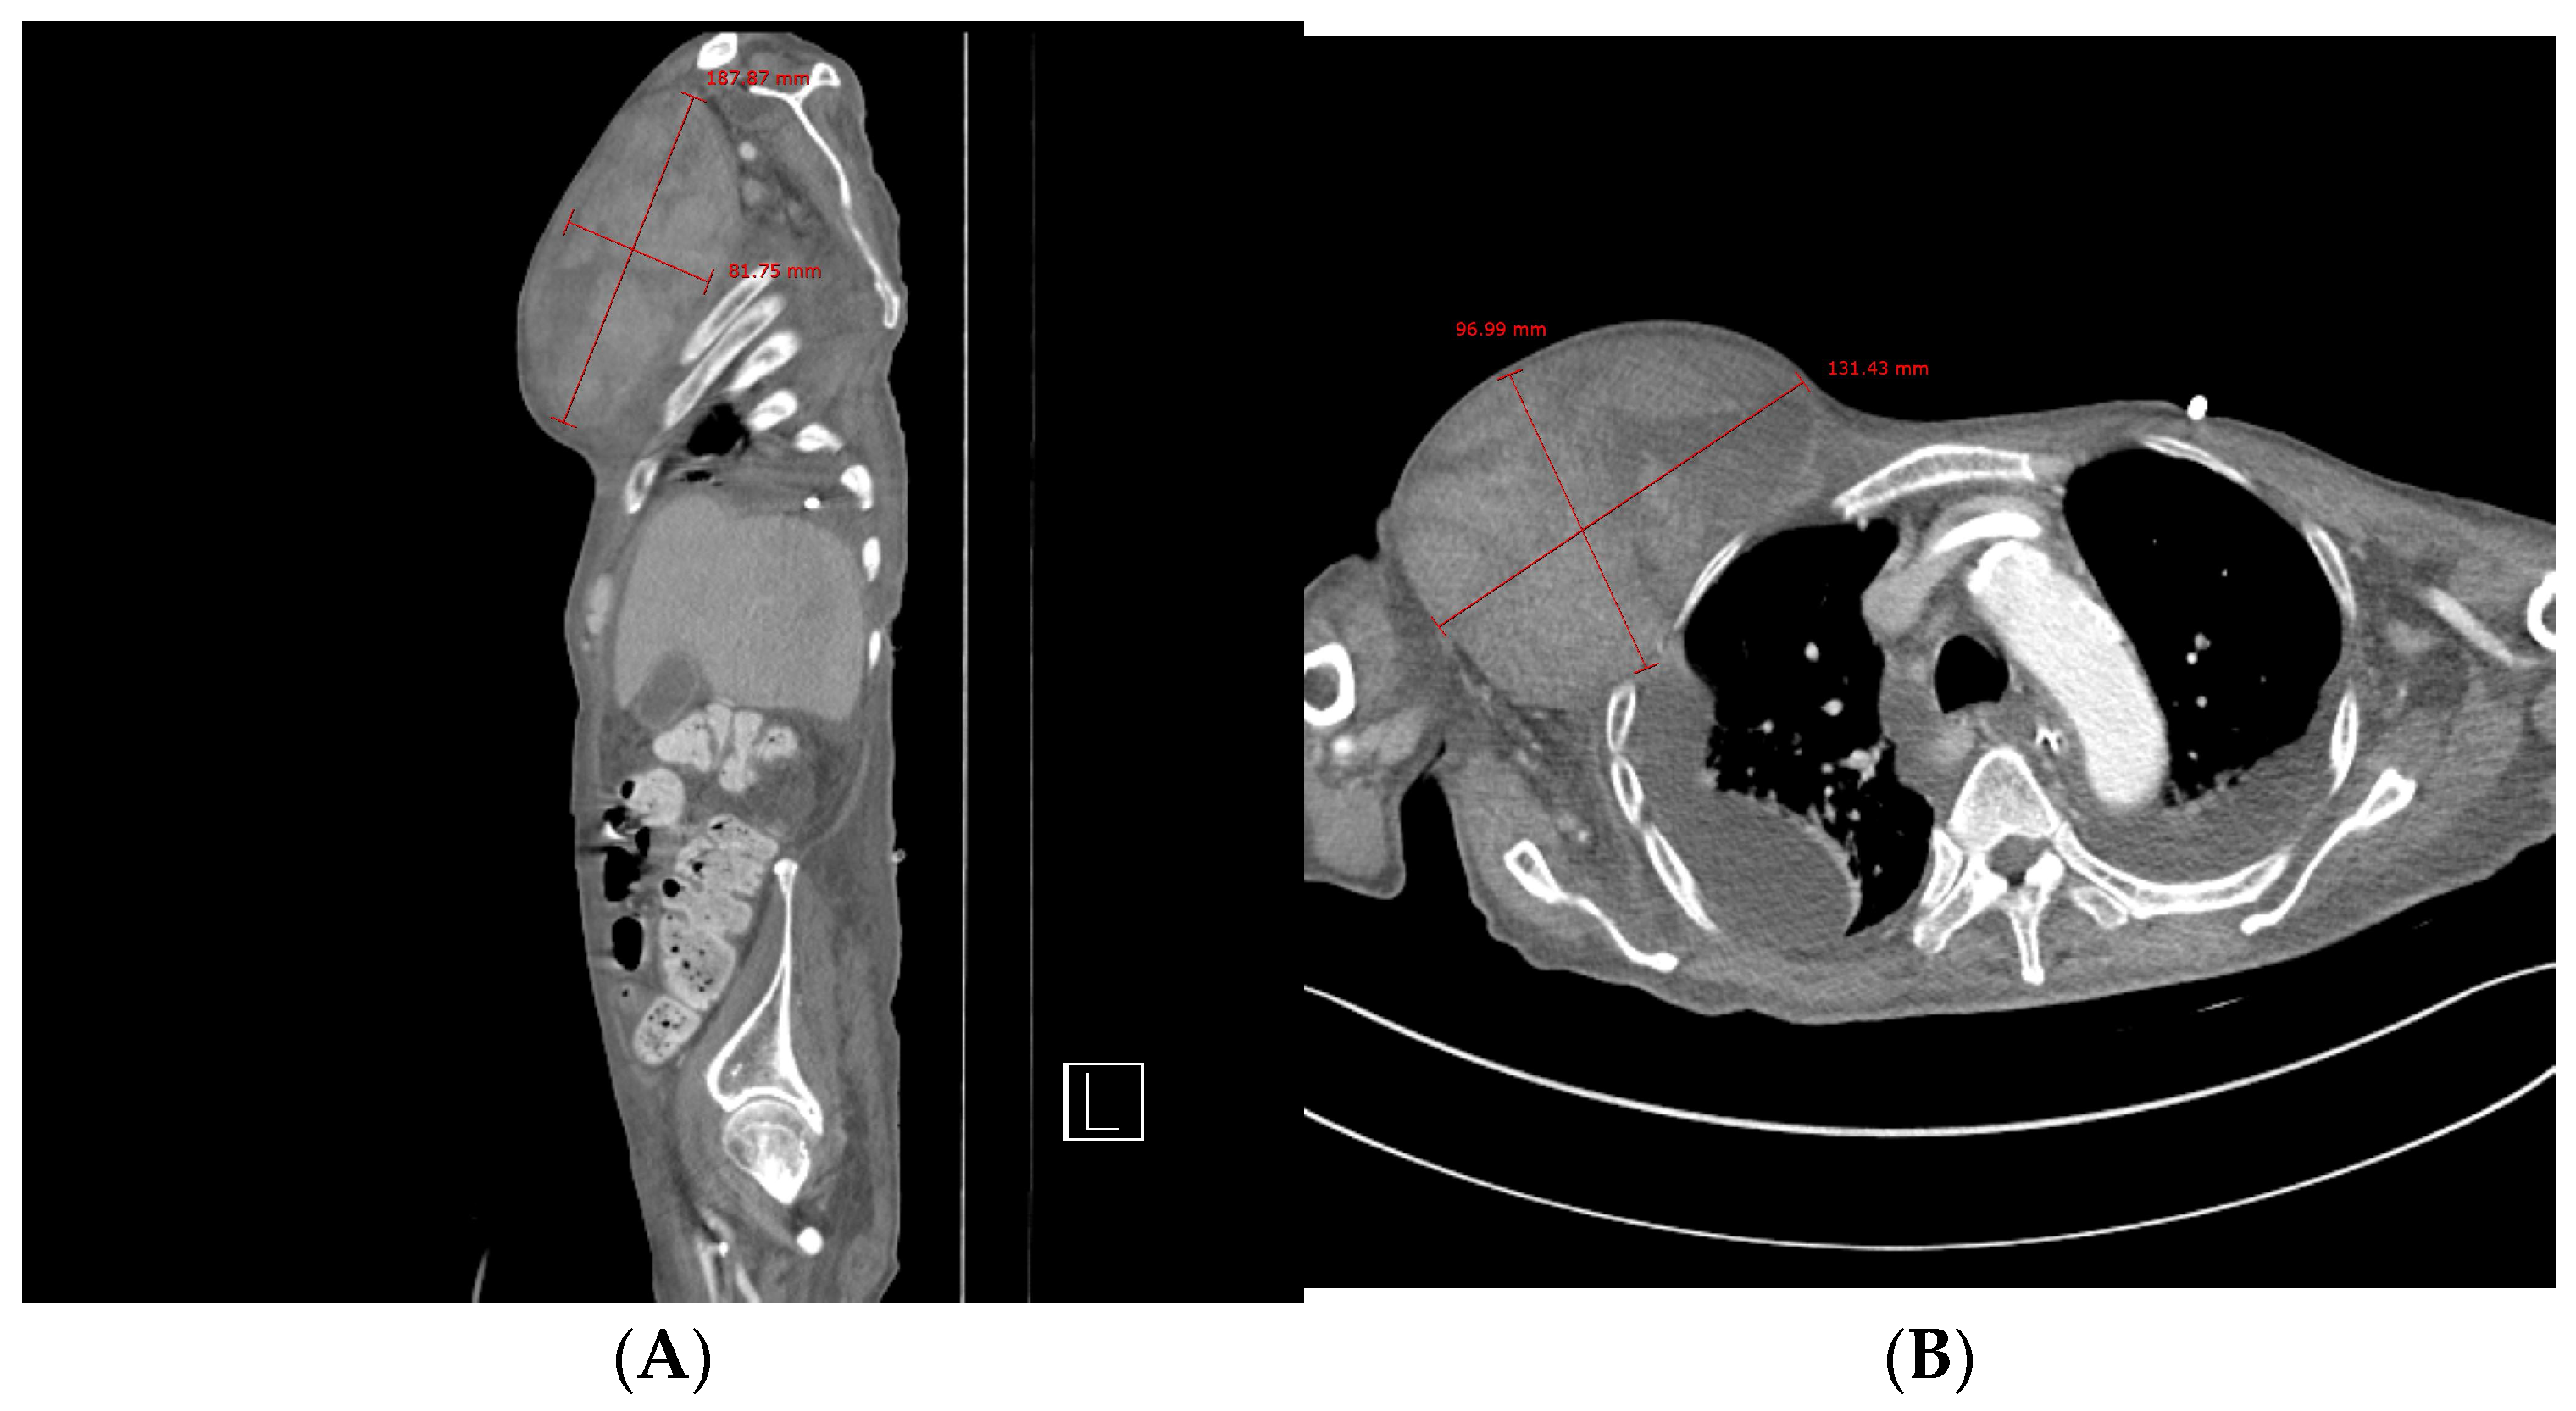

Chest computed tomography (CT) angiography revealed a newly formed 18.7 × 13.1 × 9.6 cm hematoma in the right upper anterior chest wall, with no signs of active bleeding or evidence of a pseudoaneurysm or malignant tumor (Figure 1 and Figure 2). On the fourth day post-onset, transarterial angiography was conducted via the right common femoral artery. Angiograms of the right subclavian artery, right internal mammary artery, and thoracic aorta showed no active bleeding, precluding the possibility of embolization. To manage the resulting anemia, 2 units of PRCs were transfused.

Figure 1. Chest computed tomography. (A) Sagittal view showing the formation of a hematoma measuring approximately 19 × 8 cm. (B) Axial view showing a newly formed 13 × 10 cm hematoma in the right upper anterior chest wall without evidence of active bleeding or pseudoaneurysm.